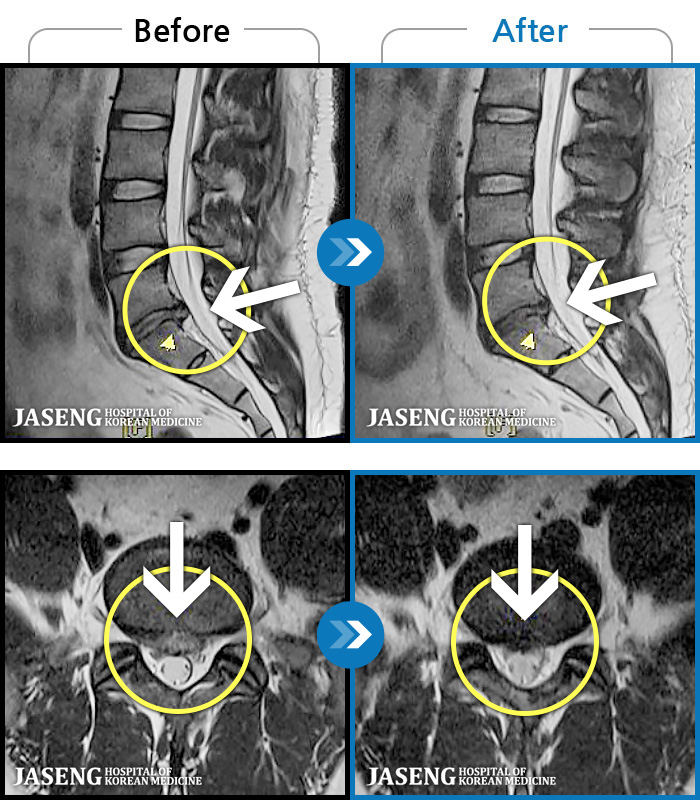

ȯںп Ǹ ǿ ԿǾ, ο ġ ۿ Ƿ ġḦ Ͻñ ٶϴ.